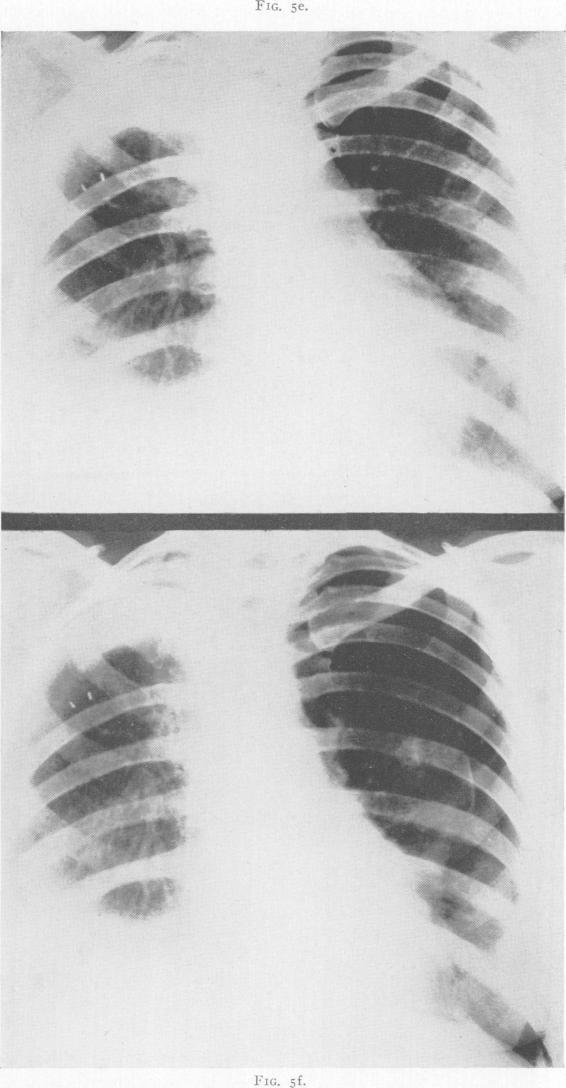

LOBECTOMY FOR PULMONARY TUBERCULOSIS.

Ann Surg. 1943 May;117(5):641-69. doi: 10.1097/00000658-194305000-00001.